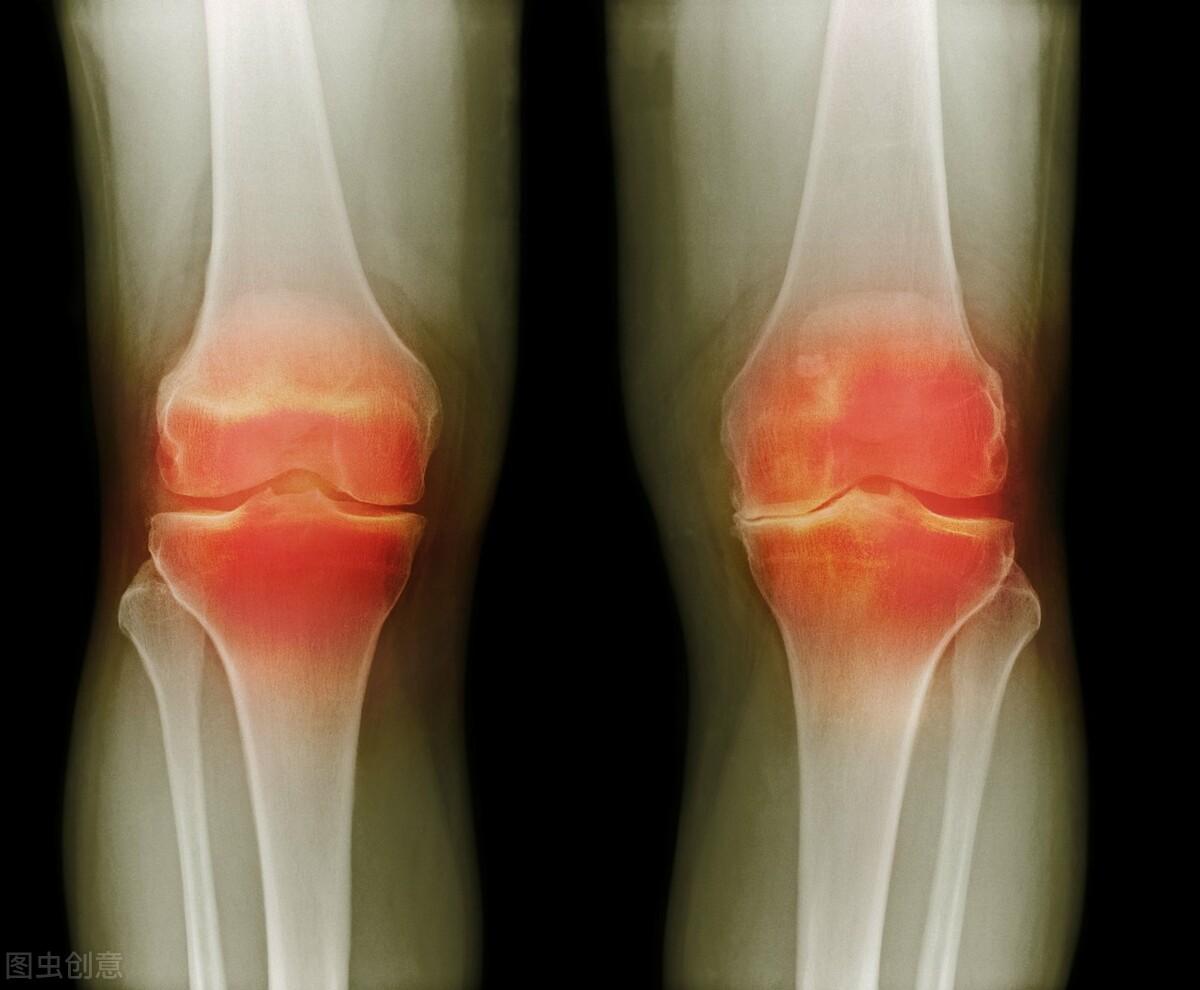

在前一段时间,我邻居家的儿子一直感冒发烧,反反复复已经好几次了,一开始只是认为普通的小感冒,于是拿感冒的症状来进行治疗,结果去医院进行检查,我邻居家的儿子发生了儿童型的类风湿,我们都以为只有老年人才容易得风湿病,那么儿童发生风湿病是一种怎样的疾病呢,如果出现了类风湿因子过高,我们应该怎么办呢?

类风湿因子正常值大约是在0到20个单位之间如果超过二十的话,证明类风湿因子偏高,那么在这个时候一定要接受医生的诊断来进行治疗,在治疗的期间一定要保证良好的心情,可以通过中医的方法来进行治疗,还可以通过饮食的方法来进行治疗。

通过以上介绍,相信各位对类风湿因子的正常值有所了解,类风湿这种疾病发生在任何年龄段上,通常来说,类风湿它属于遗传性的疾病,但是我们也可以避免发病的,在日常生活中多让患者吃一些蛋白质多的食物,增加自身的骨骼,多参加体育锻炼,提高自身的免疫力,在发病期间一些甜东西也不可以吃的。